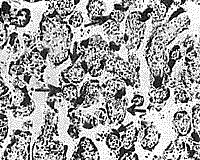

Микроскопически на плодной поверхности наблюдался ряд изменений, характерных для патологии плаценты. Так, отмечено расширение площади отложения фибриноида, а также участки некроза на материнской поверхности. В первую очередь обращала на себя внимание патология сосудов. Наряду со спазмом сосудов, отмечен склероз стенки большинства из них. Однако, наиболее характерные изменения отмечены в ворсинчатом дереве. При этом значительно увеличилось процентное соотношение всех типов патологически измененных ворсин в хорионе. Это в равной мере относилось к стволовым, промежуточным, терминальным отделам ворсинчатого дерева. Так, вместо неизмененных ворсин, занимающих в контрольной группе до 80-90% площади, увеличивалась доля склерозированных (рис. 1), отечных и фибриноидно-измененных ворсин. В случаях с мертвыми плодами — содержание их доходило до 90%.

Рис. 1. Фрагменты плаценты при сахарном диабете средней степени тяжести.

а — число склерозированных ворсин (указаны стрелками) значительно увеличено.

б — в межворсинчатом пространстве фибрин (Ф) и эритроциты (Е). х 120.